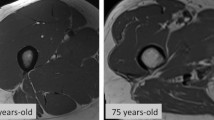

MRI is the gold standard for muscle assessment [88,89,90]. In addition, MRI is non-invasive and extremely reliable technique. MRI allows high-contrast distinction of soft tissue components (muscle, fat mass, and water) depending on anatomical compartment molecular characteristics. MRI may identify changes in muscle composition, such as muscle disruption, edema, or intramuscular adipose tissue (myosteatosis) and fibrosis (myofibrosis), as well as other biochemical indicators related to muscle quality. Intramuscular adipose tissue is made up of intermuscular and intramuscular fat. Anatomical T1- and T2-weighted sequences are often employed to assess muscle fat content. Anatomical imaging can measure CSA and muscle volume. These measures may identify hypertrophy or atrophy [91, 92]. Semiquantitative MRI muscle atrophy and fat infiltration methods have been published. The semiquantitative CT ratings may also apply to MRI (Fig. 3). Based on the amount of intramuscular fat visible on CT scans, Goutallier and colleagues were the first to describe fatty infiltration grades of the shoulder rotator cuff muscles on a five-point scale (0 = normal muscle; 1 = the muscle contains some fatty streaks; 2 = the fatty infiltration is important, but there is still more muscle than fat; 3 = there is as much fat as muscle; 4 = more fat than muscle is present) [93]. Modifications of the Goutallier classification to evaluate muscle volume and fat infiltration have recently been suggested for MRI with better reliability [94,95,96,97,98] (Fig. 4).

MRI can assess muscle amount as well as quality. Advanced MRI methods, unlike standard T1- and T2-weighted sequences, enable quantification of muscle composition and imaging of sarcopenia biomarkers [68]. By separating signal in each voxel of tissue, Dixon sequences enable for precise measurements of muscle volume and fat infiltration [99, 100]. Water-fat MRI may detect intermuscular and intramuscular fat separately. Automatic segmentation for determining whole body and regional muscle volume was suggested using Dixon MRI sequences [101]. The Dixon method is a chemical shift-based MRI sequence created to achieve homogeneous fat suppression. It consists in the acquisition of in-phase and out-of-phase images from which water-only and fat-only images are reconstructed, allowing for precise measurements of muscle volume and the degree of fat infiltration. It has the added advantage of providing both fat-suppressed and non-fat-suppressed images in a single acquisition, and it has been used in association with fluid-sensitive sequences.

MRI spectroscopy may also be used to properly assess intracellular lipid levels, which might be elevated in diseases like cancer or insulin resistance [66, 102]. MRI spectroscopy employs H1 proton signals to examine molecular tissue components. 1H MRI spectroscopy is a magnetic resonance-based chemical analytical technique which offers the possibility to specifically quantify the percentage of intracellular fat in a certain volume of interest (VOI). It is used in in organic chemistry to identify structural compounds and has the advantage of giving additional metabolic information, but it is associated with considerable sample error as a consequence of VOI position variance, because small changes in the VOI position may have a great impact on accurate fat quantification. However, is still often considered as the gold standard of volumetric fat quantification. Distinctive MR approaches for measuring subcutaneous and visceral fat, as well as fat inclusion in various tissues and organs [103, 104]. In the past, these methods were used to measure liver fat and other diseases like muscular dystrophy [105, 106]. For measuring muscle fat in sarcopenic males, Grimm and colleagues used Dixon MRI and multi-echo magnetic resonance spectroscopy [107]. The Dixon sequencing and spectroscopy indicated good correlations and accuracy for thigh fat measurements. Dixon sequences map fat distribution while spectroscopic measures localized fat. However, since MR whole-body imaging with morphological and functional imaging acquisition processes is time-consuming and expensive, it may not be practicable in most clinical settings. As a consequence, numerous anatomical, representational levels or muscles have been found as alternatives to whole-body techniques [101, 108,109,110,111]. Schweitzer and coworkers claim the third lumbar vertebra level has the most repeatability and bodily compartment connection [112]. Thigh muscles are a good candidate for MRI research because of their great magnetic field homogeneity, minimal motion artifacts, and association with physical function in older people.